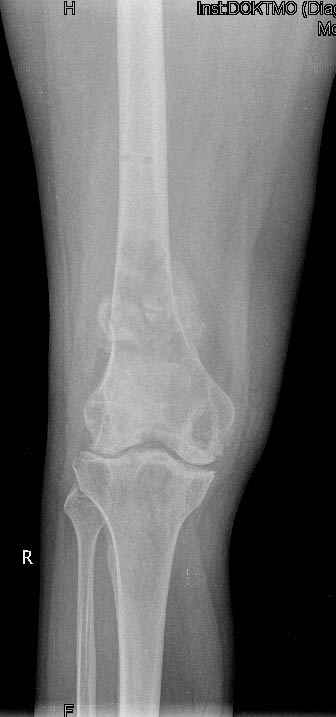

Коллеги!Окажите, пожалуйста, консультативную помощь.Мужчина, 41 год, 15 лет состоит на учете по поводу ревматоидного полиартрита, гормонзависимый (преднизолон получает нерегулярно). В процесс вовлечены крупные и мелкие суставы. 01.01.06 - без травмы наступил патологический перелом на границе н/3-с/3 бедра (перелом на фоне кистозных изменений?)

На рентгенограммах, помимо перелома, кистозные изменения на мыщелках б/берцовой кости и мыщелке бедра с другой стороны.